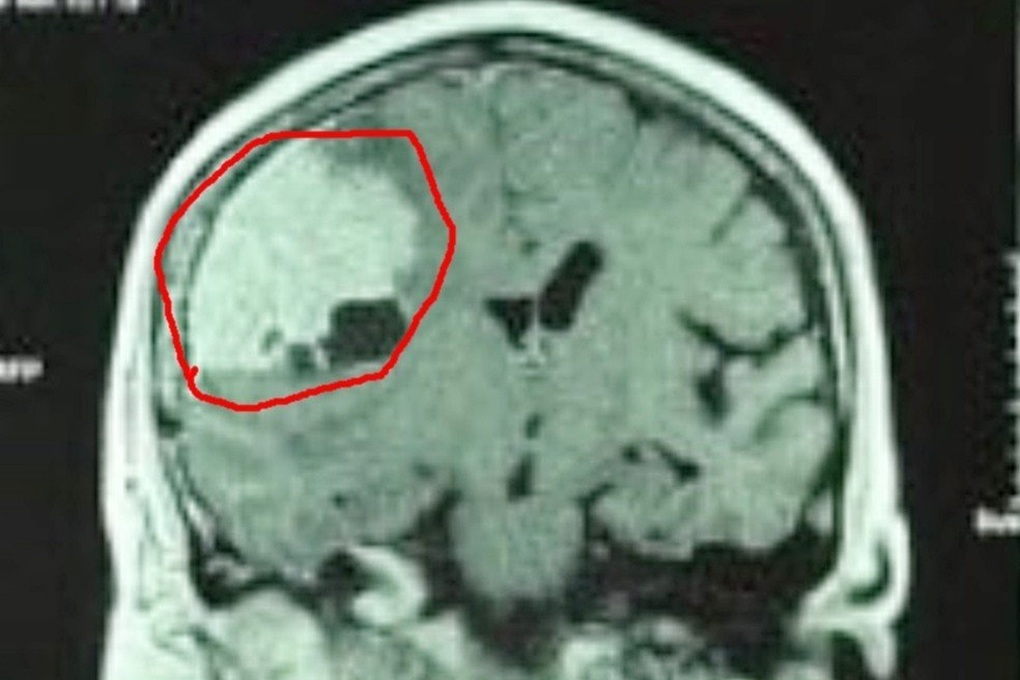

Tại đây, kết quả chẩn đoán hình ảnh cho thấy bệnh nhân có u màng não lớn vùng thái dương bên phải.

Hình ảnh chụp cho thấy khối u màng não của bệnh nhân có kích thước rất lớn (Ảnh: TC).